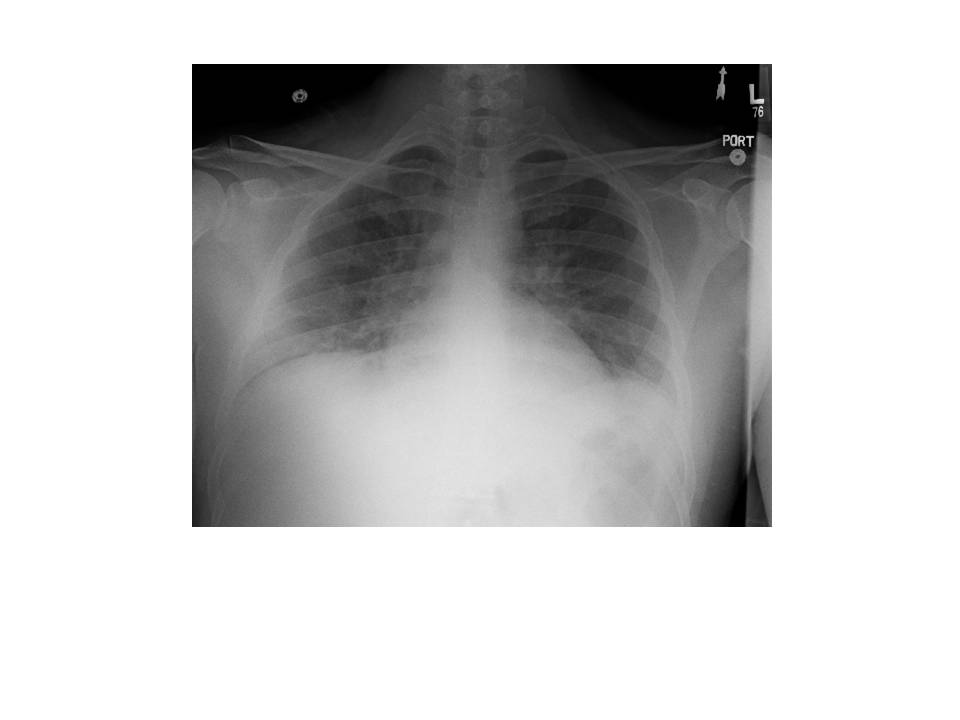

On the second day at SICU, the patient was still febrile, tachycardic, oliguric and requiring high doses of norepinephrine to maintain MAP over 70 mm Hg. Chest radiograph was unchanged and PaO2/FiO2 rate was 84. All cultures were still negative at this point.